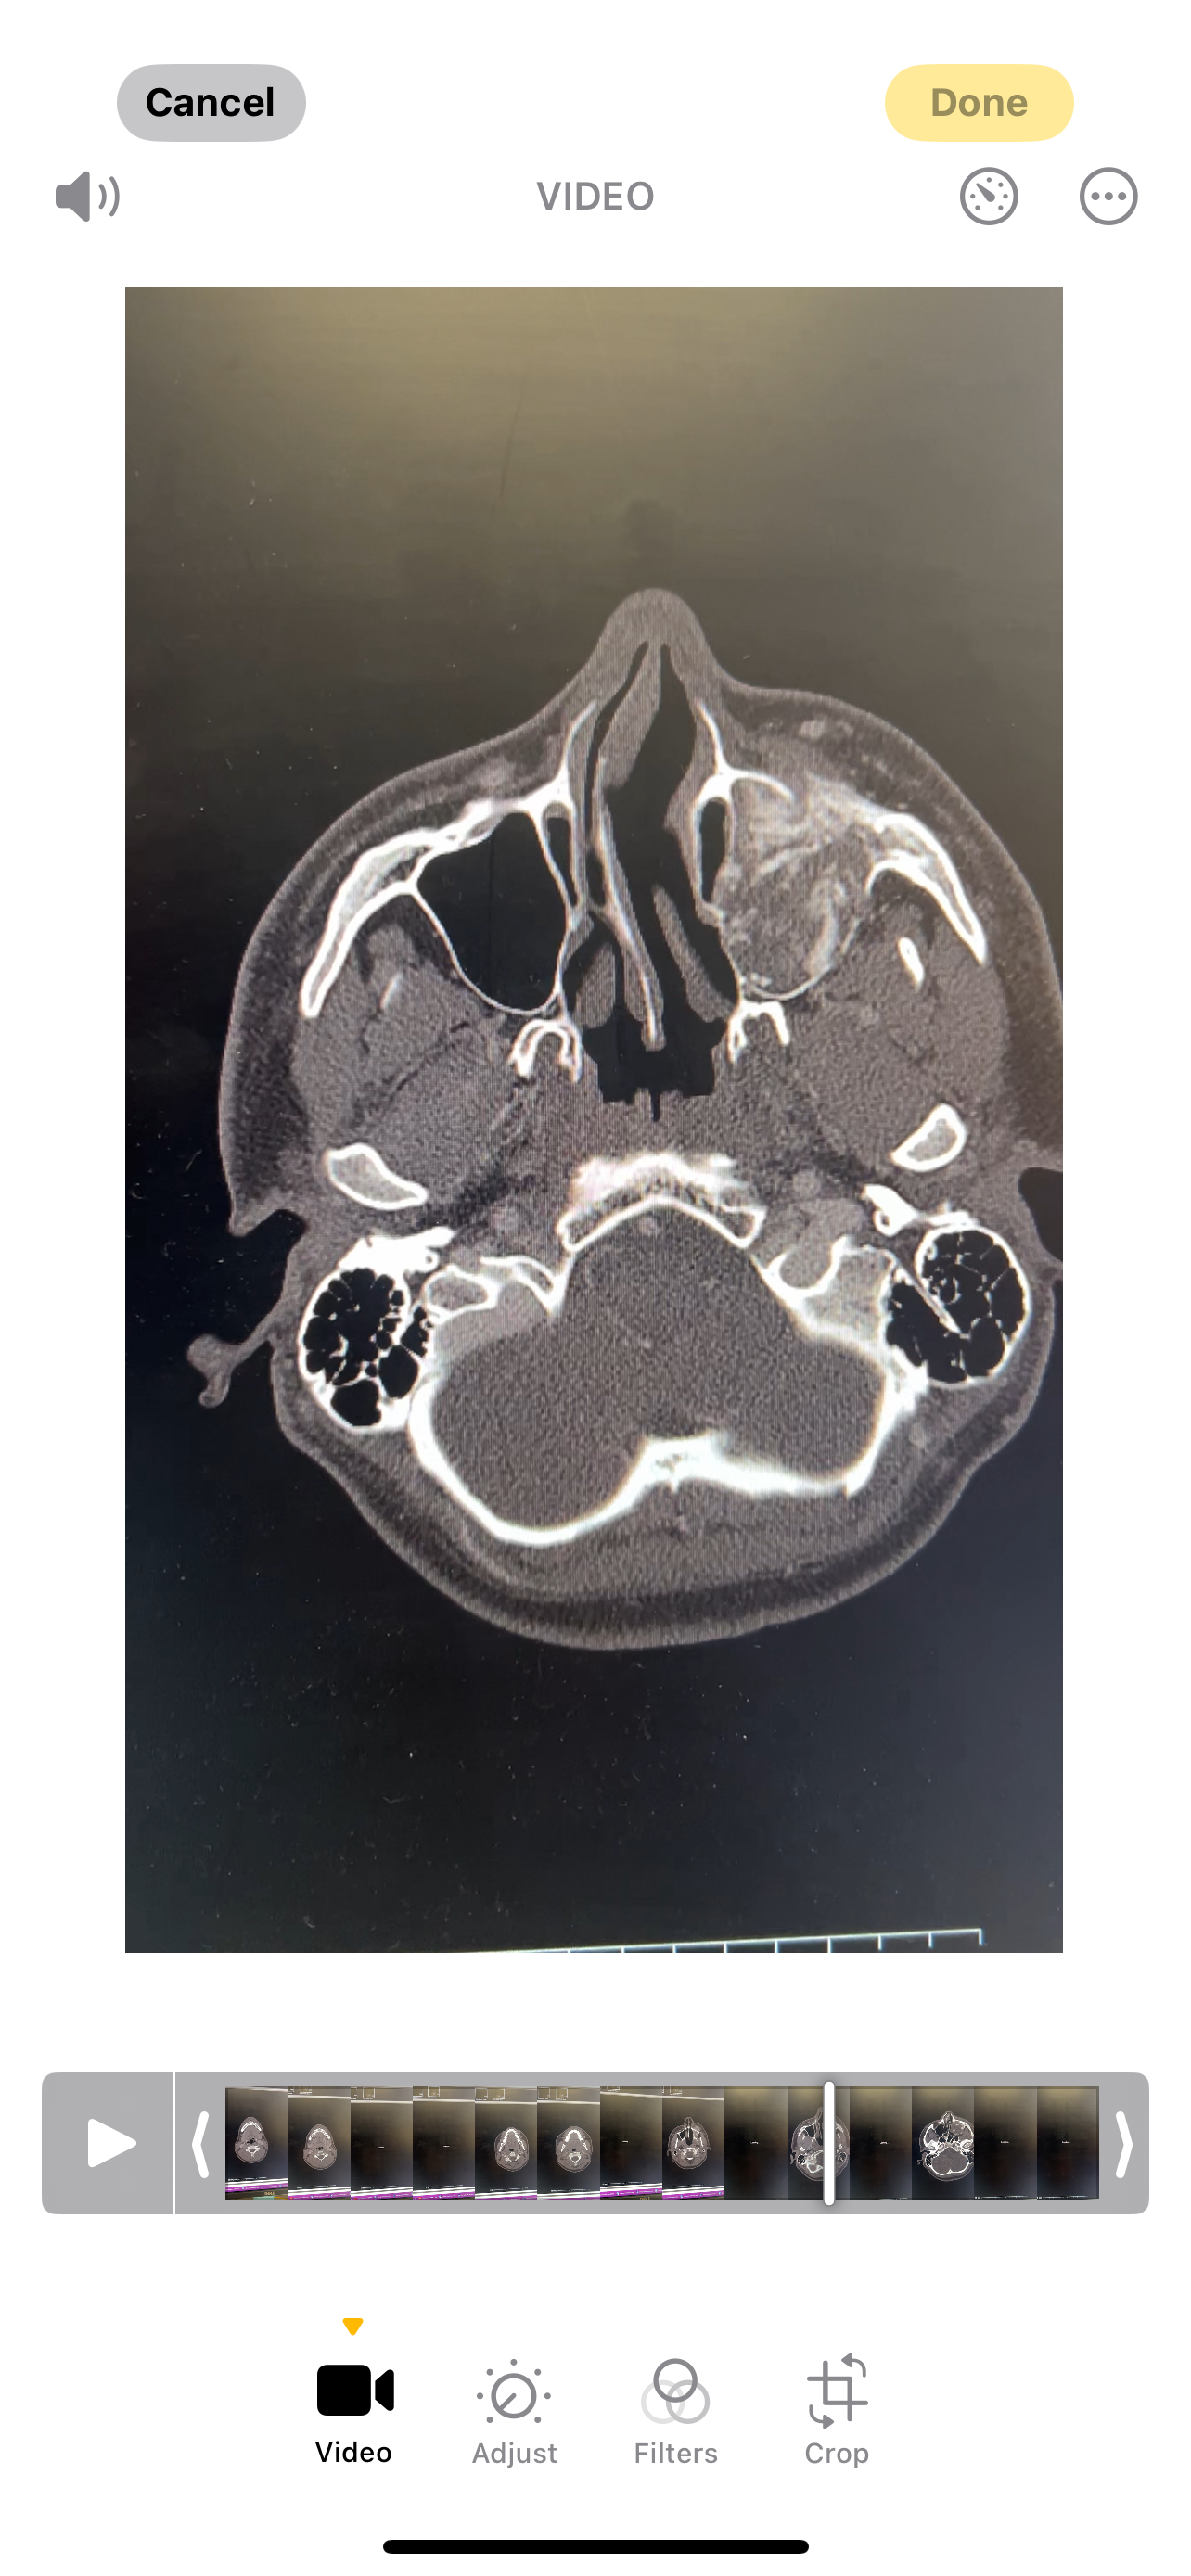

Hi everyone, we are raising money for my cousin, Sean. Sean is 25 years old and was recently diagnosed with gnathic osteosarcoma, a type of bone cancer that is located in his maxilla sinus cavity. He and his fiancé, Christa, noticed sometime in July that his left cheek had some swelling, and he was starting to have pain. They originally thought it was dental-related. He then had a CT scan of the area, and it showed some sort of mass invading his sinus cavity. A biopsy of the mass was done in early September, confirming the mass to be cancerous. Thankfully, the cancer is localized and has not spread anywhere else in his body. Since beginning his first round of chemo, Sean has lost a significant amount of weight and has sores on his throat, making it difficult for him to eat and drink. He will be undergoing additional rounds of chemo and is scheduled to have surgery in November to remove the tumor.